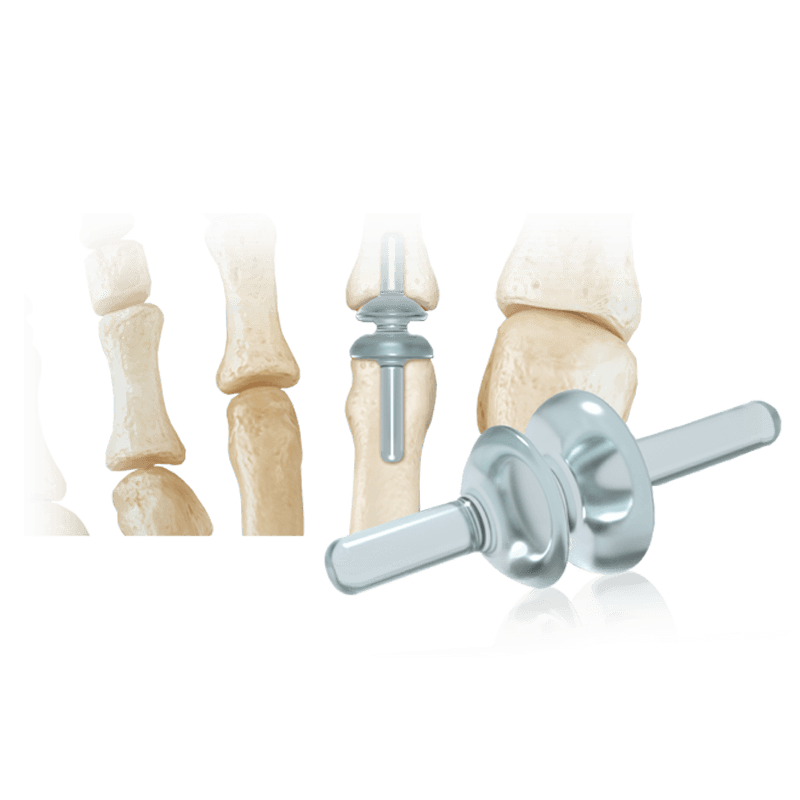

Arthroplasty

RTS® Lesser MTP

Reamer and three implant trials supplied together in a sterile, disposable kit

Implants